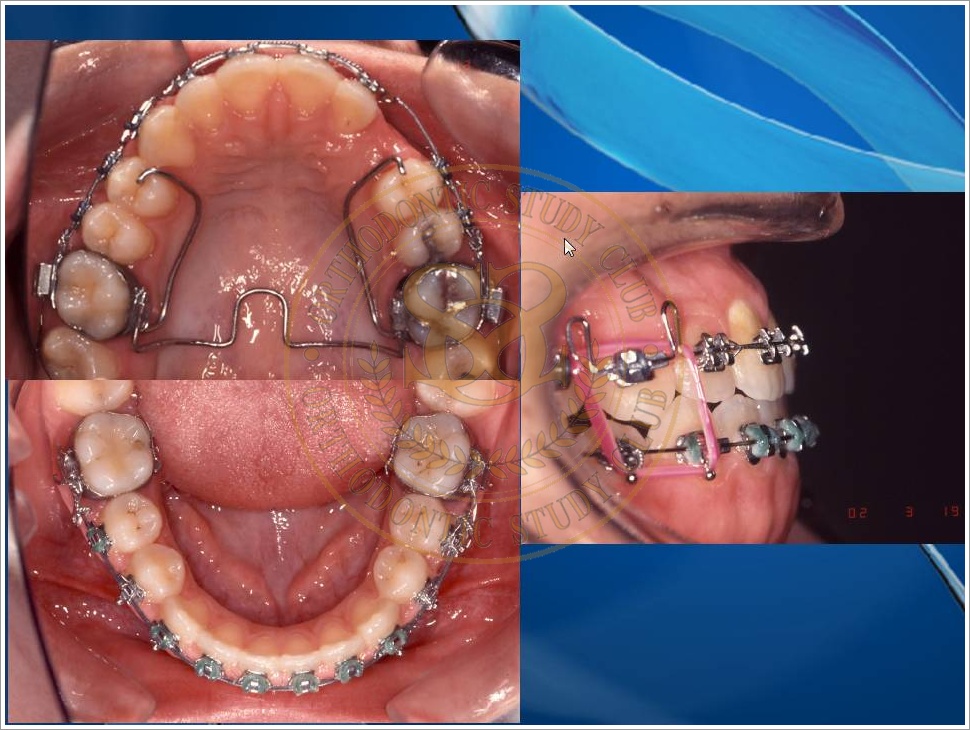

Treatment of Pseudo Class III (Class I Molar Relationship) and management of the embedded maxillary canine (Pt. Miss J.I.)